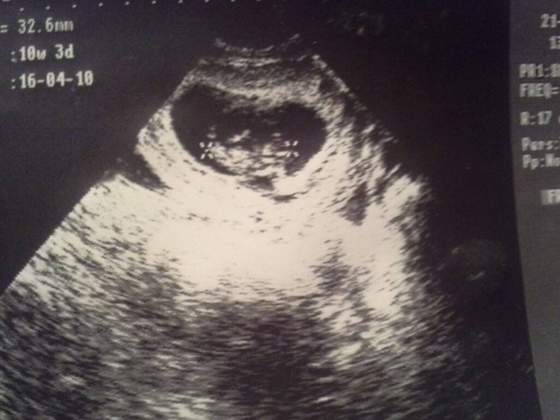

A tak wyglądała moja Milenka w 10tc :) do dziś zostały jej te długie nogi :D

Załączniki

• 1423079474425.jpg

1423079474425.jpg

24,9 KB · Wyświetleń: 48